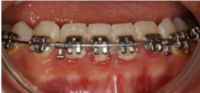

Retention

Bondad lingual retainer som håller tänderna på plats efter avslutad ortodontibehandling.

Foto: Maria Ransjö